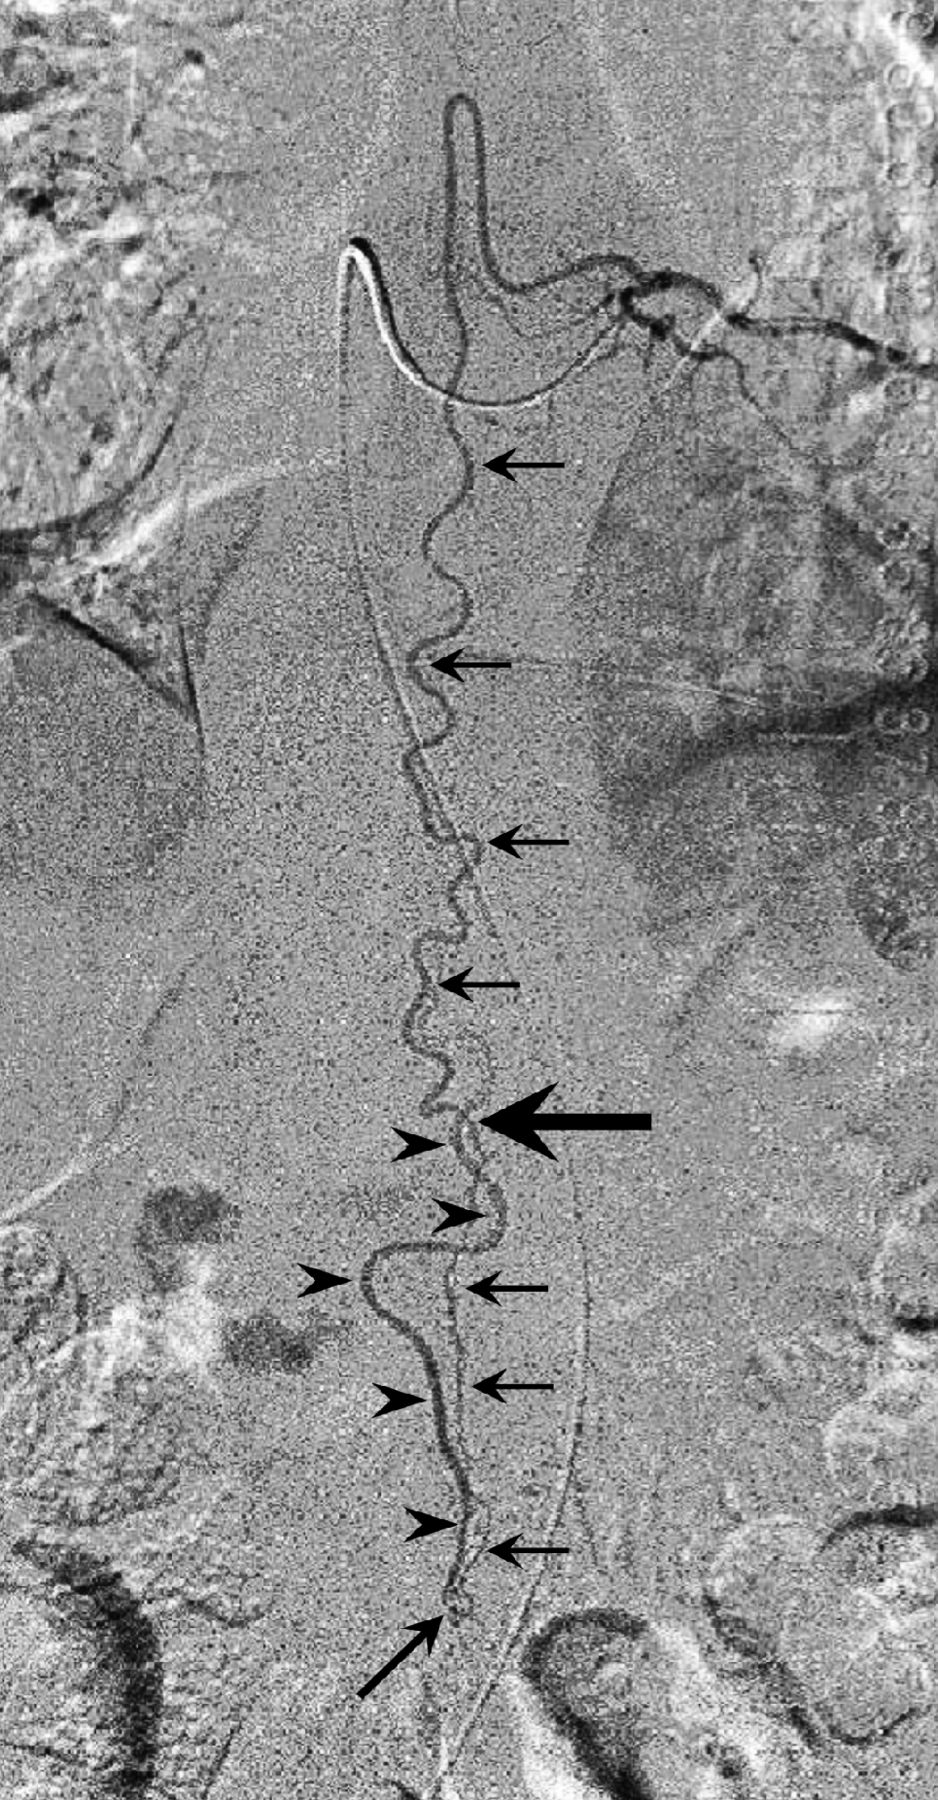

Left T9 intercostal artery angiogram in anteroposterior view shows the extension of the anterior spinal artery (arrows) traveling caudally to form an AVF at the L2 level (oblique arrow). The ascending draining vein shows a characteristic wavy pattern (arrowheads). Note the change in the course and caliber of the ASA at the conus medullaris apex (large arrow), suggesting a change of the feeding artery to a radicular artery. Reprinted with permission from Figure 2c in Tanioka S, Toma N, Sakaida H, et al. A case of AVF of the cauda equina fed by the proximal radicular artery: anatomical features and treatment precautions. Eur Spine J 2018;27(suppl 3):281–86.

Spinal angiography detected all the AVFs between the L2 and L4 vertebral levels. In 2 AVFs, caudal extension of the anterior spinal artery (ASA) was the single feeder (cases 3 and 4, Figs 1 and 2A), and a single right S1 radicular artery was the feeder in 1 (case 2, Fig 3A). Both the extension of the ASA and left S1 radicular artery were the feeders in 1 (case 1, Fig 4A, -B). In cases 1 and 3, the ASA made changes in the course and caliber at the conus medullaris apex (Figs 1 and 4, large arrow), whereas in case 4, the ASA made a straight descent without changing its caliber.

The ascending draining vein showed a wavy pattern not paralleling the feeding artery in 2 cases (cases 1 and 3, Figs 4A and 1) and a straight ascent in 1 (case 2, Fig 3A) and closely paralleled the feeding artery in 1 (case 4, Fig 2A).